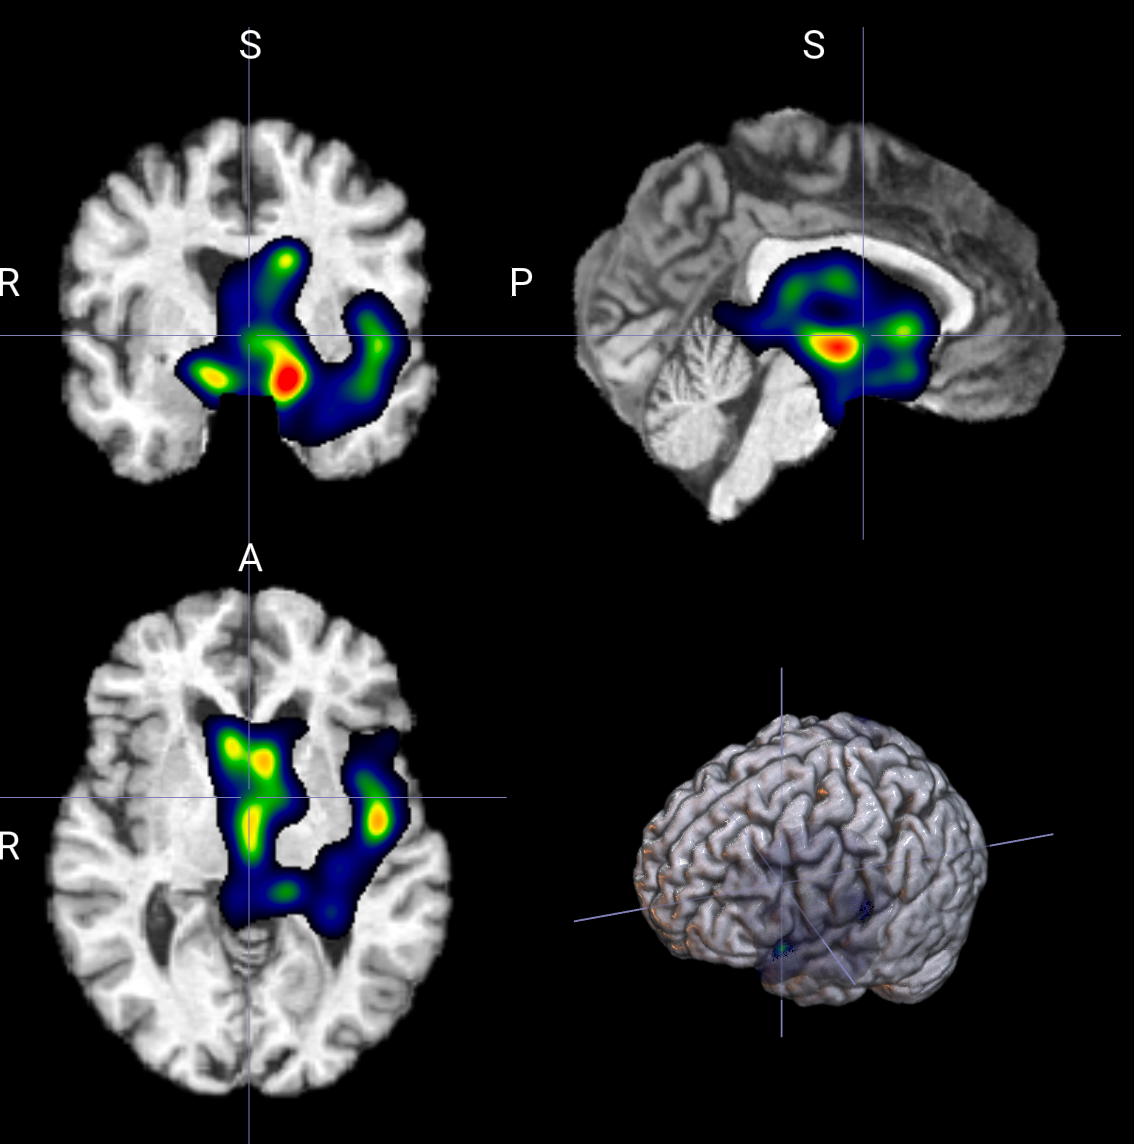

输出示例